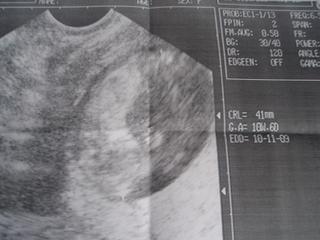

moniqe3: podobnu foto mam aj ja, v pondelok sme boli na kotrolu a tiez som bola hotova, ako malinke uz mava ruckami nozkami, hned ma potesilo na rano moj pusik malicky 🙂 v pondelok malo od hlavky po zadok 28mm 😅